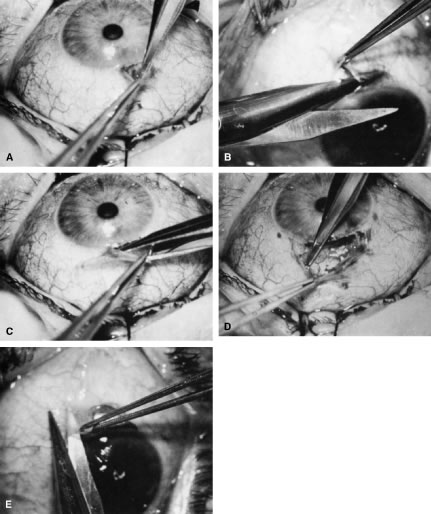

After the iridectomy is complete, the iris usually will return spontaneously into the anterior chamber unless it has suffered damage as a result of high pressure (as occurs in severe attacks of angle closure glaucoma). In patients with a reactive sphincter, it usually is necessary only to release the iris from the grasp of the incision. The iris can be stroked into position with the use of a blunt instrument on the corneal surface. Attempting to reposit the iris by directing a stream of irrigating solution into the incision is not recommended; the solution may enter the posterior chamber, forcing even more iris out of the incision. If the surgeon has difficulty restoring the iris to its proper position, injection through the previously placed paracentesis track of freshly mixed acetylcholine usually will solve the problem. In the eye with a dilated fixed pupil and a flaccid iris, it often is preferable to perform a sector iridectomy. Once the pupil is entirely round, the suture placed previously in the corneoscleral incision can be pulled up and secured promptly. Injecting balanced salt or acetylcholine solution through the previously placed paracentesis can deepen the chamber. In patients who have had recent angle-closure attacks and in whom peripheral anterior synechiae may be newly developed, forceful deepening of the anterior chamber at this point may tear open the synechiae and restore normal function of the anterior chamber. The procedure of chamber deepening must be done cautiously, with careful monitoring of IOP. A gonioprism, such as the Zeiss four-mirror lens, can be used with an operating microscope to monitor the effect on anterior chamber angle. At the close of the procedure, the pupil should be round, the chamber deep, and the incision sufficiently closed that there is no leakage. The IOP should be approximately 15 to 30 mm Hg, being raised to that level by injection through the keratostomy. Such a pressure may help prevent subsequent choroidal detachment and allows the integrity of the incision to be tested. If the corneoscleral incision has been properly placed and sutured, there should be minimal transient astigmatism. Vision should return to the preoperative level within several days. If the eye is inflamed, it usually is helpful to instill a short-acting cycloplegic agent such as cyclopentolate. Furthermore, the surgeon may give a subconjunctival injection of corticosteroid, although it rarely is necessary to do so. An antibiotic ointment and a light patch usually are applied until the facial nerve block has worn off. If there is a reasonable chance that the patient will need a filtration procedure at a later date, then the surgical procedure is modified to perform the iridectomy through clear cornea, rather than under a fornix-based flap. The technique is almost exactly the same, with the obvious exception that the incision is placed through clear cornea. Postoperative Care In almost all instances, iridectomy can be performed as an outpatient procedure. However, when associated with severe pain or when the attack of angle closure has been difficult to stop and has required extensive usage of carbonic anhydrase inhibitors and osmotic agents, admission of the patient to the hospital may be justified. Especially in older and infirm patients, the general state of health must be monitored carefully. It is important to verify that the patient has not become overly dehydrated or experienced an attack of congestive failure. The eye patch usually is removed from the treated eye as soon as the facial nerve block has worn off. If the procedure is done on an outpatient basis, a patch and shield may be left in place until the patient returns the next day for the first postoperative visit. A drop containing a corticosteroid can be used topically three or four times a day until the inflammatory response has disappeared, usually 4 to 7 days. Careful attention must be paid to the state of the pupil. The development of posterior synechiae is an important and usually unnecessary complication. Although it is not clear that posterior synechiae predispose the patient to the development of cataract, the presence of such adhesions makes extracapsular cataract extraction more difficult. Because many patients with angle-closure glaucoma will later have cataract extraction, the development of such adhesions may jeopardize the long-term visual result. Furthermore, inability of the pupil to dilate in the dark may limit the patient's visual function, especially in conjunction with a developing cataract. In most cases, dilating drops are used routinely until the inflammatory response has worn off. One acceptable program is to use tropicamide 1% at sufficient intervals to ensure that the pupil is dilated adequately for a period of approximately 1 week. The medication can be continued at bedtime for 2 to 3 weeks, or even longer, until it is certain that the inflammatory response has disappeared. Many patients are given pilocarpine preoperatively. There is a tendency to continue the administration of pilocarpine postoperatively, especially when control of IOP has been difficult. This practice should be discouraged. Pilocarpine will predispose patients to posterior synechiae and should be avoided if possible. The drug of choice for pressure control usually is topical epinephrine, a β-blocker, or epinephrine plus a β-blocker. If these two agents are not adequate, a carbonic anhydrase inhibitor can be used until the eye is entirely quiet, at which time pilocarpine can be reinstituted. In such cases, however, care should be taken to dilate the pupil periodically to prevent the development of posterior synechiae. Some surgeons may be reluctant to use dilating drops for fear of inducing angle closure. This possibility exists, but it is uncommon. Furthermore, it is preferable to know immediately whether the iridectomy has eliminated the possibility of angle closure caused by papillary dilatation. Therefore, this concern is an additional reason to use cycloplegic agents in the immediate postoperative period. Because of the possibility of an increase in IOP after dilatation, however, IOP should be checked carefully after the use of the cycloplegic agent. In addition, IOP should be monitored carefully during the initial postoperative period. Pressure spikes are not uncommon. These spikes are of little concern if the optic nerve is healthy. However, in patients with advanced glaucomatous nerve damage, such pressure spikes can be devastating; they should be avoided if possible. Postoperative evaluations ordinarily are made on the first postoperative day, after 1 week, and after 1 month. If a problem with the control of IOP is suspected, visual fields and disc photographs should be obtained. Complications The most serious complication after iridectomy is malignant glaucoma (aqueous misdirection, ciliary block glaucoma). Eyes predisposed to this complication are those with small anterior segments, typically seen in patients with marked hyperopia or small globes. Furthermore, there is some indication that eyes with high IOP preoperatively may be predisposed as well. Patients who have had an attack of malignant glaucoma in one eye are likely to have the same complication in the second eye. GUARDED FILTRATION PROCEDURES (TRABECULECTOMY) What traditionally has been called a trabeculectomy has become the standard filtration type of surgery for most cases of open-angle glaucoma. The name is a generic one, describing a wide variety of surgical methods, some substantively different from others.46–50 A goal of the original procedure was to allow filtration out of the cut ends of Schlemm's canal. In most cases, this mechanism does not appear to be the actual reason for the decrease in IOP that usually follows. Another theoretic explanation for its pressure-lowering effect, direct access of aqueous humor to the collector channels, bypassing diseased trabecular meshwork or Schlemm's canal, may be the actual mechanism for pressure reduction in a few cases. Exploration of the operative site does not disclose any area of gross filtration in some patients who have effective pressure lowering after surgery. It is likely that in such cases, aqueous humor exits into the collector channels or perhaps through the thinned scleral tissue. In most cases, the mechanism responsible for lowering IOP after guarded filtration procedure is a through-and-through fistula connecting the anterior chamber with the subconjunctival space. As such, the word trabeculectomy is a misnomer. Complete success is possible without removing trabecular tissue. Lamellar sclerokeratectomy would be a more accurately descriptive title, and it has been suggested in the past. However, the term is cumbersome and to some extent, inaccurate, because sclera is not always removed. Because the term trabeculectomy is a significant misnomer, we rarely use it in this chapter. The procedure performed currently functions as a filtration procedure; consequently, it is appropriately called a filtration procedure. When it is performed so that the filtering area is at least partially protected in an attempt to control the amount of filtration, the term guarded filtration procedure is appropriate and is used in this chapter. Consideration of how the operation actually works is not of purely academic interest; it materially affects how the surgery is performed and influences the final result. Patients with gross fistulas with filtering blebs resembling those seen with operations that were popular in the past, such as the corneoscleral trephine, usually achieve lower IOP than patients in whom the filtering bleb is thicker, more posterior, and less cystic. Furthermore, the thinner, polycystic bleb probably lasts longer, providing more years of low IOP. Consequently, if the surgeon wants to obtain IOP that is as low as possible, the guarded filtration procedure should be designed to produce gross filtration. Such a goal has its costs, however. A general principle of glaucoma surgery is that every millimeter of pressure-lowering effect has a price. This principle applies to guarded filtration procedure; the complication rate with procedures designed to produce gross filtration and lower IOP is greater than that with procedures that are more completely guarded and in which a higher final IOP is considered satisfactory, as discussed in detail in the first section of this chapter. The surgeon must carefully consider the major goal of the surgery being planned. For example, for the patient who has uncontrollable angle-closure glaucoma and is predisposed to flat chamber or even malignant glaucoma, the surgeon probably will fashion the scleral flap and suture it in place so that leakage is minimal. On the other hand, for a patient with high myopia with glaucoma that is progressive at a pressure level of 14 mm Hg, the surgeon probably will want to make the flap thin or ensure that there is leakage around the edge of the flap, or both, to have the greatest likelihood of gross filtration with a low final IOP. Factors predisposing patients to the final level of IOP are shown in Tables 14, 17, and 18. As shown in these tables, the more the surgical procedure mimics the classic Elliot corneoscleral trephine, the more reasonable to expect a final low IOP. Also, there is more likelihood of flat anterior chamber, choroidal detachment, cataract development, and a thin cystic bleb predisposing to endophthalmitis. Several modifications have been suggested for achieving a low final IOP with a reduced incidence of side effects. These include the placement of sutures so that they can be released easily in the postoperative period27,51–53 and the transconjunctival cutting of sutures postoperatively with a laser.54–57 These techniques are discussed later in this chapter. In routine cases, we prefer a limbus-based flap (Fig. 13). The development of this type of flap is only slightly more difficult than fashioning a fornix-based flap (see Fig. 11), but its advantages are significant. Compared with procedures performed with a fornix-based flap, the limbus-based operation is more likely to eliminate problems with postoperative leakage through the conjunctiva. In contrast, leakage at the cut edge of the conjunctiva of a fornix-based flap is common in the immediate postoperative period. Furthermore, cooperation under the limbus-based flap tends to be easier than with the procedure performed with the fornix-based flap. In addition, and of great importance, localized deformation of the wound in the immediate postoperative period for the purpose of encouraging filtration is performed more easily and safely when the radial grooves are covered with a limbus-based rather than a fornix-based flap. Because we often use this procedure [the Carlo Traverso maneuver (CTM)],58 the security afforded by the limbus-based flap is welcome. Thus, in most cases, the limbus-based flap is preferred. An exception is the case in which previous filtration surgery has failed and in which development of a limbus-based flap appears unjustifiably difficult and risky. Preoperative Care A careful history should be taken to determine whether systemic medical issues may affect the operative or postoperative course. For example, breathing problems and spinal arthritis may prevent the patient from lying completely flat. Chronic coughing or constipation with straining may increase the risk of postoperative suprachoroidal hemorrhage. Other relevant information includes what allergies are present and if the patient has a proclivity to excessive bleeding. Bleeding studies, such as prothrombin time, platelet count, and, in some cases, bleeding time, are appropriate in certain cases. Patients who are taking aspirin should not do so at least a week preoperatively, if possible. Similarly, anticoagulants should be discontinued long enough preoperatively to allow the coagulation characteristics to return to satisfactory levels. The eye should be as quiet as possible. Long-acting miotics, such as echothiophate, should be discontinued at least 3 weeks before surgery. If possible, pilocarpine or other short-acting miotics also should be discontinued long enough before surgery to allow their effect to wear off. Any signs of medication allergy may warrant discontinuation of the offending agent and sometimes preoperative topical steroids to quiet the inflammation, reducing intraoperative bleeding and postoperative scarring. The purpose of the surgery must be clear to the patient and the surgeon (see Table 1). Full discussion of the reasons for considering the surgery is essential, including alternative therapies and complications. Patients must understand that the usual goal of surgery is not improved visual acuity; visual acuity probably will be different and may be worse after the operation. Postoperative care must be discussed before surgery, with patients having a clear understanding of the need for continuing, careful monitoring of their condition. If it will be difficult for the patient to return to the operating surgeon, other arrangements that are satisfactory to both patient and surgeon must be made before the operation. Before the patient is sedated or anesthetized, the surgeon should again ensure that the patient's expectations and anticipations are realistic. Anesthesia Depending on the patient, surgeon, and procedure, anesthesia may range from general endotracheal anesthesia to topical agents alone. General anesthesia is reserved for patients unable to cooperate and hold still for the duration of the procedure. Retrobulbar or peribulbar injection of short- and medium-acting anesthetics, such as lidocaine and mepivacaine, with or without hyaluronidase are usually adequate. Some surgeons do not include hyaluronidase in the retrobulbar block because it may make the subconjunctival tissues boggy, complicating the surgery and making evaluation of the postoperative bleb more difficult. A facial block, such as a modified O'Brien facial nerve block,45 with approximately 10 ml of a short-acting agent, such as lidocaine or mepivacaine, may reduce lid squeezing. Most patients have only light sedation, such as 4 to 6 mg intravenous diazepam (Valium). In many cases, no sedation is necessary. Surgeons anticipating shorter, routine cases with cooperative patients may be comfortable with topical anesthesia, such as lidocaine jelly and topical tetracaine. If an iridectomy is planned, topical anesthesia may be supplemented with intracameral (nonpreserved) lidocaine 1%. Intracameral lidocaine may result in dilation of pupil, necessitating intracameral miotics before the iridectomy to prevent accidentally large iridectomies. We prefer to perform guarded filtration procedures with a modified O'Brien facial nerve blocky with approximately 10 ml of a short-acting agent, such as lidocaine or mepivacaine, in addition to a retrobulbar block with the same agent. Hyaluronidase is not included in the retrobulbar block because it tends to make the subconjunctival tissues boggy, complicating the surgery and making evaluation of the postoperative bleb more difficult. Most patients have only light sedation, such as 4 to 6 mg intravenous diazepam. In many cases, no sedation is necessary. Many patients are older, and in some, the only eye with useful vision is having surgery; therefore, the sooner the patient can be completely ambulatory after surgery, the better. In addition, in most cases, the goal of surgery is to develop a functional fistula, so it probably is helpful to remove the patch as soon as possible after surgery to encourage blinking and automassage. In some instances, especially with topical anesthesia, it is not necessary to apply a patch at all. In addition, rapid ambulation helps to ensure that the patient maintains a posture that prevents blood from settling in the area of the procedure. The use of short-acting agents and minimal sedation encourages prompt return to full normal function, an important consideration in the older person with sensory deprivation. Operative Technique The limbus-based conjunctival flap should be developed as far superiorly in the superior fornix as possible (Figs. 13 and 14). The conjunctival incision should be sufficiently far posteriorly that it involves the thick tissue overlying the superior rectus muscle; if it is made more anteriorly, the likelihood of leakage through the incision increases. This leakage is especially a problem when agents specifically used to combat postsurgical scarring are employed. Toothed forceps, or even serrated forceps with indentations that are sharp enough to cut the conjunctiva, should not be employed. On the other hand, a common error is to forget the normal elasticity of the conjunctiva and consequently to neglect to stretch the tissue sufficiently to permit clear identification of the edges of the incisions. This problem is a special concern with Tenon's capsule, which tends to retract out of the operative field, and may be overlooked unless specific attention is paid to bringing it into view. To facilitate a posterior incision, a superior rectus bridle suture may be placed and gently affixed to the drape. A second alternative is the corneal traction suture. A 7-0 Vicryl suture is placed through the peripheral cornea, approximately 0.5 to 1.0 mm from the limbus. The suture should be placed at least ½, but not full thickness, with plane of the spatulated needle parallel to the surface of the cornea in midbite, so that the cutting sides of the suture do not create tracks that may facilitate cheesewiring through the cornea. The eye is then rotated inferiorly, the suture entry and exit from the cornea checked for leakage indicative of an inadvertent full thickness passage, and the suture affixed to the drape with two pieces of tape, folding the suture of the first to prevent slippage. Sterile adhesive medication labels work well. The incision in the conjunctiva and Tenon's capsule should be long enough to permit easy retraction of the tissue toward the limbus, providing good visibility. A 10-mm incision is average. It is better to have the incision longer than shorter. If the initial incision is made directly over the insertion of the superior rectus muscle, it should not be carried deep into the tissue, because the muscle could be cut. Rather, the edge of Tenon's capsule and conjunctival tissue should be held firmly, and the underlying tissue separated with blunt dissection. The scissors should be tilted anteriorly toward the limbus to avoid the underlying muscle and the rich vascular network surrounding it. The blunt dissection is continued until Tenon's capsule is completely incised. A second approach is to make the incision in the supertemporal or supernasal quadrant, 8 mm or more posterior to the limbus, through conjunctiva and Tenon's capsule down to bare sclera. This approach avoids the risk of immediate damage to the muscle with bleeding. The scissors are then used bluntly spread and dissect the plane between Tenon's capsule and the sclera horizontally, parallel to the limbus, over the superior rectus. One blade of the scissors is then placed above the conjunctiva, and one beneath Tenon's and the wound enlarge parallel to the limbus. As the incision is enlarged, traction on the internal blade of the scissors away from the globe stretches the tissues over that blade, allowing careful inspection. Before making this enlargement of the wound, the surgeon must ascertain that the superior rectus is not within the tissue to be cut by the scissors. Tenon's capsule, with its conjunctiva, is spread anteriorly over the cornea to give the best view possible of the corneal scleral sulcus. In almost all instances, there is a thin layer of episclera remaining. This layer is grasped and elevated forcibly, permitting development of a 2 × 2-mm buttonhole, through which the bare sclera is easily visible. This episcleral tissue is markedly adherent. The buttonhole should be extended approximately 5 mm temporally and laterally. The forceps are used to grasp the edge of this deep episcleral tissue, and pull it anteriorly and inferiorly, so the surgeon can clean down to bare sclera anteriorly to the corneoscleral sulcus. The sulcus is not readily visible until the episcleral tissue has been reflected from it. In fact, it probably is the single most important landmark with regard to filtration surgery. As seen in Figure 4, the conjunctiva inserts just anteriorly to the corneoscleral sulcus. Dissection to that point can be carried out with relative ease, and with meticulous technique, even 1 mm or so anterior to the groove. More anterior to that, conjunctiva has metamorphosed into the epithelium of the cornea, and attempts to develop a conjunctival flap over the cornea itself are doomed to failure. Furthermore, the trabecular meshwork usually lies near the corneoscleral sulcus. In large eyes, which are common in myopes, a perpendicular incision just anterior to the corneoscleral sulcus would enter the anterior chamber well anterior to the iris root. In contrast, in small eyes, which are found in most hyperopes, an incision at the same point also would enter the anterior chamber but just in front of the iris root. When these eyes have extensive peripheral synechiae, an incision made with a sharp blade through the corneoscleral sulcus will penetrate into the posterior chamber, which obviously is not the location for most glaucoma procedures. Consequently, in small eyes with small anterior segments, especially in association with angle closure, the surgeon must place the corneoscleral incision more anteriorly than usual and be certain that the incision actually is entering the anterior chamber. In such cases, it may be necessary to shelve the incision anteriorly. This problem clearly affects patients with acute or chronic primary angle-closure glaucoma. We prefer to clean the conjunctiva meticulously until no fibers are crossing the corneoscleral sulcus. The most effective method is to use a no. 67 Beaver blade held at a 45-degree angle from the direction of the incision. Only the pointed tip is used to cut the tissue (see Fig. 13A). The dissection is continued anteriorly until the conjunctiva can no longer be cleaned further anteriorly. The corneoscleral sulcus should be free of fibers for a width of approximately 4 to 5 mm. Partial cleaning of the area posterior to the corneoscleral sulcus can be accomplished in a variety of ways, including grasping the Tenon's episclera and pulling it anteriorly and inferiorly, scraping the surface of the sclera in a semiblunt fashion with the edge of the blade, and pushing the tissue with the tip of a Weck-cell sponge (Xomed-Treace, Jacksonville, FL) or similar dry sponge. Such techniques almost always are only preparatory, and they do not clean the sulcus adequately. We emphasize this point because a frequent cause of failure of filtration procedures is blockage of the site of attempted filtration as the result of an excessively posterior incision, and the usual cause for an excessively posterior incision is failure to reflect the conjunctiva-Tenon's episclera sufficiently anteriorly. Some surgeons excise Tenon's capsule, especially where it appears to be redundant or particularly profuse. This practice is thought to increase the rate of success and to result in a thinner, more cystic conjunctival filtration bleb. Few studies have evaluated the advantages and disadvantages of this technique. However, it has the disadvantage of predisposition to a thinner, more fragile covering to the filtering bleb, with a greater incidence of postoperative complications, and it does not appear to result in lower IOP.59,60 A fornix-based approach, beginning with a peritomy, may also be used. The conjunctiva can be cleaned from the limbus by making an incision directly at the limbus at approximately the 11 o'clock position and performing a peritomy clockwise to approximately the 1 o'clock position (see Fig. 11). The addition of a relaxing incision at the 11 o'clock position allows better visibility and improves the closure. The limbal area is cleaned meticulously, and the conjunctival-Tenon's tissue is undermined to facilitate final closure of the fornix-based flap. The corneal epithelium directly at the limbus between the 11 and 1 o'clock positions should be removed 1 mm anterior to the limbus. Wet-field cautery is an excellent instrument for this. Care should be taken to test the power level of the cautery on the sclera or gently at the limbus first, to prevent unintended thermal damage to the cornea. High cautery settings may thus create astigmatism, but this usually reverses in days to weeks during the postoperative period. After the limbal area has been meticulously cleaned, either with a fornix-based or a limbus-based flap, light cautery outlines the position of the scleral flap (Fig. 15B). The shape of the flap is unimportant but in the routine case. We prefer one that is approximately 2 mm wide circumferentially and 3 mm long radially. This rectangular flap is easy to dissect and involves relatively little scleral tissue. A no. 67 Beaver blade is used to incise the sclera in the area outlined by the cautery. This incision should be at least half and preferably two thirds the thickness of the sclera. Magnification of the operating microscope usually is increased during the creation of the scleral flap. If the surgeon is right handed, the right-hand posterior corner of the scleral flap is grasped with a forceps such as the Pierce-Hoskins forceps. This instrument has indentations but no teeth and, therefore, is not likely to penetrate or tear the scleral flap. Even in cases in which the surgeon wishes to develop a thin scleral flap, it is preferable to start the dissection with a thick flap, at least one half the scleral thickness (see Fig. 13C). As the surgeon proceeds, the flap can be thinned to the proper thickness. The no. 67 Beaver blade may be used to dissect the flap. The knife should be held as parallel to the brow as possible, because this position facilitates dissection of the flap (see Fig. 15D). Finer, sharper “superblades” are useful when making very small scleral flaps. The thickness of the flap must be monitored carefully as it is developed. The surgeon should be careful never to dissect blindly but always must see the tip of the knife. Flipping the flap forward and back, so that the surgeon sees the outside and then the inside, can help in estimating the thickness of the sclera. The assistant should be diligent in sponging to keep the view of the dissection as clear as possible. We prefer to keep the scleral flap dry rather than to irrigate it; irrigation tends to hide the landmarks at the depth of the flap. Firm traction should be placed on the scleral flap that is being developed so that cutting is performed against traction. The flap is extended for at least 1 mm and preferably 2 mm anterior to the junction of the white sclera with a clear cornea (see Fig. 15E). Once the flap has been developed, and before the anterior chamber is entered, a paracentesis is formed with a short, sharp, disposable 25-gauge needle (see Fig. 5). We believe that the placement of this paracentesis track is vitally important. An alternative method is a stab type, uniplanar, temporal paracentesis. The stab-type paracentesis tends to leak more as balanced salt solution is instilled, which may make evaluation of fistula outflow more difficult. However, this paracentesis is more easily accessed, both intraoperatively and postoperatively and may be helpful if postoperative anterior chamber reformation is necessary. The anterior chamber is entered by incising through the sclera in a radial fashion, along the right-hand line of radially placed cautery. Multiple light scratches are placed, and the blade is kept vertical so that entry will be as close as possible to the anterior extent of the scleral flap. A sharp blade such as a diamond knife or superblade can be employed, but unless used with a guard, these blades are likely to penetrate into the iris. These sharper, more pointed blades make it possible to enter more anteriorly, which is a real advantage. But they must be used cautiously to avoid damage to the iris and lens, with subsequent development of cataract. The incision is made long enough so that its posterior edge is just posterior to the junction between the white sclera and the clear cornea. If the posterior extent of the incision is not long enough at the time of entry, the incision is lengthened. Vannas scissors are placed into the anterior chamber, with the surgeon making certain that the tip neither penetrates into the iris nor splits the sclera. This entry is assisted by lifting the area to be excised with a fine forceps, such as a Pierce-Hoskins forceps, and depressing the bed of the sclera with the edge of the Vannas scissors. The scissors must not be directed in an angled fashion so that they extend through the iris into the lens and underlying zonules. After the radial groove has been made, the block must be excised. There are advantages to cutting the anterior aspect of the block first, and advantages to cutting the posterior edge of the block first. To some extent, the method that is used depends on each eye and what occurs at the time of the surgery. Once the Vannas scissors is placed so that one blade is definitely in the anterior chamber, it can be moved anteriorly as far as possible so that it pushes firmly against the base of the scleral flap, where it is attached to the cornea. In the right eye, it usually is easier to use the right hand to hold the Vannas scissors. The left hand is used to fix the sclera at the posterior edge of the bed. The left hand pulls the globe superiorly in the direction of the brow, and the right hand pushes the Vannas scissors inferiorly toward the nose. The goal is to ensure that the section is placed as far anteriorly as possible, so that no ledge of cornea will be left. The blade of the Vannas scissors should be held exactly perpendicular to the cornea so that the cut is not shelved. The outer blade should be directly over the inner blade, as shown in Figure 15G. Once the anterior aspect of the block has been cut, the fixation on the posterior edge of the bed is released. The assistant who is holding the scleral flap anteriorly to ensure adequate visualization continues to hold the flap firmly. The left hand holds the anterior edge of the block and pulls it anteriorly (inferiorly) toward the nose. The Vannas scissors move posteriorly (superiorly) toward the brow, and the posterior edge of the block is incised. Again, the surgeon holds the scissors absolutely vertically so that the sclera will not be cut. Just as the anterior aspect of the block was incised all the way to the radial groove, the posterior block is incised all the way to the nasal radial groove. The surgeon changes hands, holding the Pierce Hoskins forceps in the right hand and the Vannas scissors in the left hand. The block is held with the right hand and amputated with the Vannas scissors, leaving the desired amount of ledge, usually 0.25 to 0.5 mm. When the block is removed, it should be inspected (see Fig. 15H). If it is not exactly rectangular with edges that are completely unshelved, then it has not been taken properly. The surgeon should note the error so that it can be corrected at the next surgical procedure. The corneosclera to be excised does not include sclera posterior to the scleral spur. Thus, there is no chance of performing a cyclodialysis and much less of a chance of injuring the large vessels that form such a rich plexus where the ciliary body attaches to the scleral spur. A second approach to anterior chamber entry and ostomy creation is to use a sharp blade to make an incision parallel to the iris at the far anterior extent flap bed, under the flap. Keeping the blade parallel to iris, entering similar to the creation of the phaco-tunnel, reduces the risk of damage to the lens and iris. A sclerocorneal punch, such as a Kelly-Descemet punch, is then introduced parallel to the iris, under the flap, through the incision. The punch is then rotated vertically so that it is perpendicular to the bed of the flap. The punch is then used to make several bites, usually near the temporal side of the flap bed, to create an ostomy. After each bite the punch is removed and the excised piece is wiped off with a sponge, and the punch reintroduced. Experience with the punch and care not to use excessive posterior pressure allows for the gentle creation of an ostomy of the desired dimensions with sharp, vertical edges. How much ledge the surgeon wishes to leave and how thin the surgeon wishes to fashion the scleral flap should have been determined carefully before surgery. These decisions will depend on the desired postoperative result (see Table 16). The thinner the flap, the lower the pressure; the smaller the ledge, the greater the likelihood of postoperative flat anterior chamber. An iridectomy is performed (see Fig. 15I). To ensure that the iris tissue does not plug the guarded filtration procedure site, the iridectomy should be large enough so that no edge of the iris is visible through the area of excised sclera. The scleral flap is sutured in place with 10-0 nylon. The suture is placed at a 45-degree angle to both the posterior and the radial edges, so that as the suture is tightened, the scleral flap will return to its proper position. An additional suture is placed at the other posterior corner (see Fig. 15J). Scleral flap sutures should be ½ to 2/3 thickness through the peripheral ½ mm of the flap. This reduces full-thickness holes through the flap that may allow excessive leakage. Longer bites on the scleral side allow easier suture isolation and viewing for possible postoperative laser suture lysis. Unless it is clear that there has been much scleral contraction and that the scleral flap has not closed adequately, at this point, the anterior chamber is filled with balanced salt solution through the previously placed paracentesis (see Fig. 15K). The surgeon monitors carefully the IOP with a finger placed on the cornea. If the anterior chamber cannot be formed readily, then additional sutures are placed until that can be achieved (see Fig. 15L). If the anterior chamber forms readily and the globe becomes firm, the surgeon tests the area of the procedure with sponges to determine whether fluid actually can leak through the radial edges (see Fig. 15L). Leakage through the posterior edge of the flap is undesirable because that portion almost always will scar closed, at which time the procedure will fail. Leakage, minimal or marked, through the radial incisions is the surgeon's goal. The amount of leakage is adjusted appropriately by applying cautery to shrink the edges of the radial incision or by placing additional sutures. It has not been determined whether the actual amount of leakage of aqueous humor through the sclera affects the final level of IOP. However, it certainly affects the immediate postoperative course, and it probably affects the final IOP. When leakage is marked, so that the anterior chamber collapses spontaneously, the eye is predisposed to flat anterior chamber and hypotony, two undesirable postoperative complications. When there is no leakage, the eye is predisposed to excessive elevation of IOP postoperatively; although this elevation is an undesirable complication, in almost all cases, it can be handled by removing a releasable suture or cutting a laserable suture. We prefer to close the scleral flap sufficiently tight so that when balanced salt solution is injected through the paracentesis, the IOP will be raised to approximately 30 to 40 mm Hg. After the injection is stopped, the IOP ideally should fall gradually to approximately 10 to 20 mm Hg and remain in that range. If the scleral flap has been fashioned improperly so that it is too thin and contains tears, it may not be possible to close the flap tightly enough to maintain the desired level of IOP. In such cases, a viscoelastic material may be injected into the anterior chamber. However, we prefer not to use viscoelastic materials routinely. In practice, this method rarely is employed but may be used particularly in cases with extremely high preoperative pressures, requiring higher early postoperative pressures to reduce the risk of complications. If the surgeon does not believe that sutures will be able to be released with a laser, externalized releasable sutures should be used (see Fig. 7). If the pupil can be dilated, atropine 1% is instilled at this point and repeatedly to ensure that it is dilated at the conclusion of the operation. If a fornix-based flap was developed at the start of the guarded filtration procedure, the corner at the 11 o'clock position is pulled forcibly counterclockwise so that the cut edge of the conjunctiva completely covers the area of the scleral flap. This corner is sutured into the episclera immediately at the limbus, with care taken to avoid the episcleral blood vessels. A purse-string technique is used to ensure a watertight closure. A 10-0 nylon suture can be used. Some surgeons prefer to use an absorbable suture such as 9-0 PDS, but these sutures are more likely to produce a foreign body sensation in the postoperative period. The relaxing incision is closed with a running suture so that the conjunctiva is pulled tightly over the sclera and the incision is watertight. A running mattress suture also may be used but usually is unnecessary. If a mattress suture is used, it must be placed so that the conjunctiva is stretched firmly to prevent leakage. Some surgeons prefer to close with two “wing-type” sutures, one at either side, placed just anterior to the limbus with the tissue stretched firmly between them. Some surgeons pass these sutures twice through the conjunctiva and cornea to reduce early suture slippage. A purse string may be used to close any “dog-ears” at the lateral edges. If a limbus-based flap has been performed, the incision is closed in two layers. Tenon's capsule is sutured to Tenon's capsule, with care taken to avoid penetrating the conjunctiva. This closure is facilitated if the surgeon starts at the right-hand side of the incision and proceeds clockwise, locking the running sutures. Four to six locked sutures usually are adequate. The suture is exteriorized through the apex of the conjunctival incision, and the conjunctiva is closed in a counterclockwise fashion with multiple running sutures. The surgeon should be careful to approximate the edges of the conjunctiva together without including the underlying Tenon's capsule. The sutures are placed approximately 1 mm apart to ensure a watertight closure. We prefer to use a soft suture such as 8-0 Vicryl on a vascular needle. Other appropriate suture materials are 9-0 Vicryl or 9-0 PDS. Another option is 10-0 nylon, but this material is technically more difficult to use, tends to be more difficult to pull up tightly, and predisposes to leaking incisions. Silk suture should be avoided because this material predisposes to fistulas. After the conjunctival flap has been closed, a 30-gauge blunt needle on a bottle of balanced salt solution is placed through the paracentesis into the anterior chamber, and balanced salt solution is irrigated into the anterior chamber (see Fig. 15M). As this irrigation is done, the surgeon's index finger should monitor the firmness of the pressure of the globe. The IOP should not rise above 40 mm Hg as the irrigation is performed. The IOP, however, should rise, and if some firmness does not develop in the eye, say a pressure of 10 mm Hg, additional sutures should be placed. As the saline is injected, a bleb should develop overlying the scleral flap (see Fig. 15M). This bleb should continue to enlarge as the surgeon continues to irrigate into the anterior chamber. At the end of the procedure, the eye should have a well-closed conjunctival flap without extruding Tenon's capsule and without leakage; a totally formed anterior chamber; an adequately dilated, round pupil; and a satisfactory conjunctival bleb (see Fig. 15N). If the eye does not look right at the end of the surgery, the result probably will not be as good as the surgeon and the patient would like. In some cases, subconjunctival betamethasone 3 mg may be injected deep into the inferior fornix. Caution should be used to ensure that it does not dissect up underneath the conjunctival flap superiorly. Modifications of Technique The surgeon should alter the technique according to the desired goal (see Table 16). A surgeon who is considering releasing sutures postoperatively by burning them with a laser, usually will place a 10-0 nylon suture in the middle of the posterior edge of the scleral flap. This approach will permit release of the sutures on either corner of the scleral flap with a laser while maintaining the integrity of the incision and preventing excessive leakage. In some cases, the surgeon may believe that it will not be feasible to release sutures with the laser. When the conjunctiva is thick or scarred, or when there may be subconjunctival bleeding, it may be impossible to see the sutures clearly enough so that they can be released with a laser. In some cases, the tissue may be too thick to permit laser cutting, and releasable sutures are recommended. If the surgeon wishes to obtain low IOP postoperatively, the guarded filtration procedure can be changed to a full-thickness procedure by removing all of the sutures in the sclera flap. If that is the surgeon's goal and there is a reasonable likelihood that the sutures will not be able to be cut with a laser postoperatively, then all of the sutures should be placed in a releasable fashion. Because suture release is often important to the success of the surgery and because it is not always possible to cut sutures with a laser, we prefer releasable sutures. One technique for using releasable sutures is shown in Figure 7. The basic principle is to place the suture so that the ends are exteriorized, permitting easy release postoperatively. USE OF AGENTS THAT ALTER INFLAMMATION AND WOUND HEALING Probably the most significant change in the technique of glaucoma surgery in the past 10 years has been the introduction of agents that strongly affect the way wounds heal.28–34,61–76 It has been known for many years that postoperative scarring is one of the major causes of unsuccessful filtration procedures. Efforts to alter postoperative inflammation use a variety of techniques, including corticosteroids and nonsteroidal anti-inflammatory agents, irradiation, and agents such as heparin. However, the introduction of 5-FU by Heuer and co-workers30 at the Bascom Palmer Eye Institute represented a major step forward. The carefully done collaborative study sponsored by the National Institutes of Health established without doubt that 5-FU administered postoperatively results in lower IOP by promoting filtration. Since then, many other agents have been studied, including weaker and less dangerous substances, such as trifluridine, which was shown by Katz and co-workers74 to produce a small decrease in IOP in comparison with untreated cases, and more potent agents, such as mitomycin, which was studied by Chen in Taiwan and Skuta and colleagues76 at the University of Michigan, and others.69,70,75 Indications (see Table 19) This discussion is limited to three agents—corticosteroids, 5-FU, and mitomycin—not because these are the only agents, or the best ones, but because they represent a spectrum offering the ophthalmologist a wide choice and because they are the most extensively studied agents. Nonsteroidal anti-inflammatory agents applied topically do not appear to have a beneficial effect on glaucoma filtering procedures and are not indicated in the postoperative care of patients who undergo glaucoma surgery. Because 5-FU and mitomycin result in lower IOP in many patients and because there is current interest in achieving lower IOP than in the past, many surgeons tend to conclude that 5-FU or mitomycin should be used in association with most, if not all, glaucoma surgery. Some surgeons recommend these agents not just in cases in which a less than satisfactory result is expected, but in all cases, including primary cases. This practice is, in our opinion, unwise. The lowering of IOP achieved by 5-FU and mitomycin comes at a cost. The short-term inconvenience or short-term side effects are less of a concern than the long-term effect on the eye and, most importantly, the patient. The goal of glaucoma surgery, as discussed earlier, is not to lower IOP but to help restore the wholeness of the patient. When antimetabolites result in low IOP, they do so by encouraging filtering blabs that are thin, ischemic, and highly elevated. Corneoscleral trephines and other similar full-thickness procedures tended to produce this type of bleb, and this tendency led surgeons such as Cairns46 and Watson50 to develop alternative methods of surgery. The blebs occur in patients who undergo full-thickness filtration procedures and in those in whom antimetabolites are used. These blebs predispose patients to endophthalmitis, approximately 1% per year when the bleb is located superiorly. In addition, eyes with high, thin blebs leak aqueous through the bleb, with resulting unpredictably low pressures. The Seidel test originally was developed to determine whether a bleb was working properly, that is, leaking aqueous through the conjunctiva. Blebs that occur after antimetabolite administration often have positive Seidel test results. This problem predisposes patients to endophthalmitis and a variety of other problems. Hypotonous eyes have unstable refraction, which results in disturbing changes in vision. In addition, especially in younger patients, macular edema develops in a significant percentage of eyes with IOP of approximately 6 mm Hg or when IOP is lowered 6 mm Hg or more.27,50–52 This hypotony-macular edema syndrome may occur with IOP as high as 12 mm Hg, although it usually is limited to eyes with much lower IOP. Among the most serious problems facing patients who have high, excessively filtering, thin blebs, and the type of bleb that results from 5-FU and mitomycin administration are photophobia and discomfort. For example, the pressure in the eye is 6 mm Hg, and, although the surgeon may be delighted, the patient is miserable. These problems are especially common when the filtering blebs are not underneath the upper lid. In such cases, the development of a dellen adjacent to the bleb is routine and usually is associated with significant disability. Surgeons who use antimetabolites in glaucoma surgery also should discuss the potential risks with the operating room and nursing committees in their institutions. At the Wills Eye Hospital, these agents are treated in the same manner as any carcinogen: Any material with which they come in contact is handled as if it is radioactively contaminated and is discarded in containers designed for radioactively contaminated materials. Antimetabolites The more potent the antifibrosis agent, the greater the potential for both help and harm.27,28 Although 5-FU is less effective than mitomycin in developing successful filtering blebs, the long-term side effects of 5-FU, both ocular and systemic, also are less serious than those of mitomycin. Similarly, 5-FU is more effective and has fewer side effects than topical corticosteroids. Consequently, there is a theoretic justification in matching the type and dose of antimetabolites (wound healing suppressants) with the anticipated likelihood of failure of the procedure. The greater the likelihood of failure, the more potent the agent to be used. Tables 17 and 18 list some of the factors that predispose to success and to failure. The optimal dose has not been established with certainty. These considerations are covered more fully under the discussion of each agent. Topical Corticosteroids The use of topical corticosteroids is an essential part of almost all glaucoma surgery. Inflammation must be prevented as much as possible in all glaucoma surgery, whether it is laser iridectomy or a Molteno shunt procedure. The dose-response relationships of topical steroids have not been studied extensively in glaucoma surgery, but there is little evidence that administration of topical corticosteroids in doses that exceed the equivalent of prednisolone acetate 0.1% four times daily is significantly beneficial. The response appears to be biphasic. When inflammation appears to be significant, or the predisposition to inflammation is great, administration of corticosteroid eye drops as frequently as every hour may be indicated for several days. However, the propensity of eyes with open-angle glaucoma, as well as several other types of glaucoma, to have a steroid-induced rise in IOP should be recalled, and the complicating nature of this rise in pressure on the postoperative course kept in mind. In addition, topical corticosteroids can produce cataract. The effect of fluorometholone and some of the newer congeners of fluorometholone, which appear to have less propensity to cause elevation of IOP, have not been studied adequately. They may offer a theoretical advantage, but the current drugs of choice are dexamethasone phosphate 0.1%, prednisolone phosphate 1%, or prednisolone acetate 1%. A satisfactory routine for most patients who have undergone uncomplicated filtration procedures is prednisolone acetate 1% four times daily for 2 weeks, three times daily for 1 week, twice daily for 1 week, and then once daily for 1 week (Table 22).

Table 22. Typical Postoperative Schedule*

*This schedule is a guideline only. Actual treatment will vary in relation to many factors, such as access to care, state of the eye, and general health. †For example, tropicamide or cyclopentolate. ‡Onset of severe pain is an indication of a complication. §Examination should include estimate of anterior chamber depth, visual acuity, and ophthalmoscopy.

Subconjunctival corticosteroids may cause subconjunctival bleeding. Their routine use can be neither recommended nor discouraged because they have not been studied adequately. They appear unnecessary for routine cases. However, repository steroids are contraindicated because they may cause an intractable elevation of IOP, requiring surgical removal of the steroid. Some glaucoma surgeons have used systemic corticosteroids for many years. These agents have significant systemic risks, and their use in routine cases cannot be recommended on the basis of clinical studies. We use oral steroids in our surgical patients extremely rarely. 5-Fluorouracil The optimal schedule for using 5-FU has not been determined. Furthermore, although it is apparent that the agent works more effectively in some patients than in others, it is not known how to identify patients in whom 5-FU has its greatest effect. It is reasonable to assume that the patients with the greatest likelihood of surgical failure are those in whom the drug must be used most vigorously. Related factors are listed in Table 19. There are two major methods of application: intraoperative and postoperative. INTRAOPERATIVE USE. Major advantages of the intraoperative use of 5-FU include its ease of administration, the avoidance of postoperative injections,62,65,66,81 and a significant decrease in side effects, especially corneal side effects, that are associated with postoperative injections. The main disadvantage is the increased seriousness of a complication, such as a leaking conjunctiva. A limbus-based flap should be used when 5-FU is given intraoperatively, because it is difficult to close fornix-based flaps in a way that ensures that they will not leak. The incision in the conjunctiva should be made as high in the superior cul-de-sac as possible, over the insertion of the superior rectus muscle. Conjunctival incisions that are made preparatory to limbus-based flap procedures for any type of filtration procedure should be placed in this area. When an antimetabolite is not used, the surgeon has a greater margin of error because of the tendency of the eye to heal itself. The surgeon does not have this luxury when using an antimetabolite. All personnel who use 5-FU or mitomycin should wear disposable gloves and other appropriate equipment. A fluid-retaining sponge, such as a Weck-cell sponge, is fashioned to be approximately 3 × 3 mm in length and width, and about 0.5 mm in depth. The sponge is soaked in 0.1 to 0.2 ml of 5-FU that has been withdrawn directly from an undiluted vial of 5-FU. The 5-FU concentration should be 50 mg/ml. The sponge is placed on the sclera over the area of the scleral flap. The sponge is left in position for 5 minutes. The conjunctiva is pulled over the sponge so that the Tenon's capsule side of the conjunctiva is in contact with the sponge impregnated with the 5-FU. The sponge is removed with a forceps that can be passed off of the tray, and the sponge is discarded in a container designed for disposal of toxic material. Fluffs are placed around the eye to absorb the irrigating solution, and the eye is irrigated with 5 to 15 ml of balanced salt solution. The fluffs and other contaminated materials are discarded in the special container. The nurse dispensing the 5-FU and the assistant picking up the fluffs wear disposable gloves before irrigation is done. After the 5-FU has been irrigated and the eye cleaned completely, the disposable gloves are discarded, and the procedure continues. Some surgeons prefer to make the radial and posterior scleral grooves first, and to develop the scleral flap before applying the 5-FU. This approach has the advantage of delivering a more concentrated dose of 5-FU deep into the sclera. Its disadvantage is that the material cannot be used if the flap is made improperly so that the anterior chamber is entered. The scleral flap usually is fashioned so that it is at least one third of the thickness of the sclera. Thinner flaps tend to leak excessively, predisposing patients to unwanted flat anterior chambers. It is inadvisable to use 5-FU if there is a possibility that the agent can get into the anterior chamber. Releasable or laserable sutures, or both, can be employed. However, the time at which sutures are cut differs from the suture cutting time when an antimetabolite is not used. The effect of suture cutting in eyes that have been treated with 5-FU tends to be more dramatic than in cases in which the antimetabolite is not used. Furthermore, it is possible to cut the sutures as late as 1 month postoperatively and still have a significant effect. This situation never occurs in patients who have not been treated with antimetabolites and whose sutures must be cut within 10 days or, in some cases, as early as 5 days, if cutting the sutures is to have a significant effect. The amount of flow through the scleral flap is checked carefully, as it is in all patients who undergo guarded filtration procedures. However, here, it is doubly important. If the anterior chamber cannot be reformed easily when balanced salt solution is injected through a paracentesis track into the anterior chamber, additional sutures are placed until the goal can be achieved. At the end of the operation, as with all filtering procedures, balanced salt solution is injected through the paracentesis track. The injection is continued until the bleb becomes greatly elevated, approximately 180 degrees superiorly. After the bleb is elevated, sponges are used to test the incision and inspect the conjunctiva to ensure that there is no leakage. If the surgeon is not completely confident about the surgical technique or is relatively inexperienced in using 5-FU or performing guarded filtration procedures with antimetabolites, it is best to paint the conjunctiva and incision with fluorescein and examine the patient's eye under a blue light to determine whether there is any leak age. Leakage must be corrected (see discussion of complications). An additional technique, used now by some of us, is to raise a bleb inferotemporally about 3 to 5 mm posterior to the limbus with a highly cohesive viscoelastic material. The 5-FU is then placed by inserting the no. 30 needle on the syringe containing 0.3 ml 5-FU through the bleb of viscoelastic and advancing the needle cautiously towards the nasal aspect of the globe, injecting the 5-FU slowly. This develops an area of conjunctival elevation in front of the needle tip, helping avoid penetrating the conjunctiva. The remaining contents of the syringe are then injected, making a bleb inferonasally. POSTOPERATIVE USE. Initially 5-FU was used as an adjunct to glaucoma surgery by subconjunctival administration during the postoperative period.28,30–34,63,64,68,71–73 The initial dose increased the success rate significantly, but it was associated with significant side effects, most of which were related to the cornea. Attention to the method of administration can reduce the side effects dramatically. Using a 30-gauge needle and making sure that it is introduced for a distance of at least 1 cm is important; after the injection, the eye is irrigated copiously. In addition, in many cases, fewer injections are needed than were used in the initial study. Before administering 5-FU, disposable gloves are placed on both hands. The 5-FU is drawn directly from the vial of 5-FU as it comes from the pharmacy. The vial contains 10 ml of 5-FU 50 mg/ml. The conjunctiva is anesthetized by multiple instillations of topical anesthetic or, preferably, by the placement of a pledget of anesthetic that remains in the inferior cul-de-sac for 5 minutes. The 5-FU 0.1 ml is drawn directly from the vial into a tuberculin syringe. The needle is removed and replaced with a short, sharp, disposable 30-gauge needle. With the patient seated comfortably at the slit lamp, and the eye anesthetized, the needle is placed in the subconjunctival tissue, usually in the inferior cul-de-sac, and advanced so that the tip is at least 1 cm away from the point of entry. The further the needle can be introduced under the conjunctiva, the more likely it is that the 5-FU will not leak out from the needle puncture site. This leakage from the needle puncture site is the major cause for corneal complications that are related to the use of 5-FU when it is given by injection. The frequency of injection of 5-FU varies with the need to suppress postoperative inflammatory response. The patient is examined carefully after the surgery to verify that there is no buttonhole, tear in the conjunctiva, or other contraindication to the use of the 5-FU. If there is no contraindication, then the injections may be given on the first postoperative day and then for a total of 5 to 10 injections. One satisfactory routine is to give the injections every other day for 2 weeks, although some prefer to give them daily for 1 week. It is not known which routine works best. If corneal decompensation occurs, the injections usually are stopped until the cornea has cleared, although the corneal changes are not an absolute contraindication to the continuing use of the 5-FU. Mitomycin Mitomycin is given intraoperatively in the same manner as 5-FU.34,75,76,82–84 The major differences involve dose and time of administration. Because they are the group most likely to have hypotonus maculopathy, mitomycin is used with particular caution in young myopes. However, when the surgeon is convinced that a filtration procedure is the optimal approach, and a good limbus-based conjunctival flap can be developed, mitomycin may be appropriate. However, its ability to cause serious ocular damage and its uncertain intraocular effects must be kept in mind.77–80 We perform a limbus-based flap when using mitomycin. All personnel using mitomycin should double glove. Concentrations of 0.2 to 0.5 mg/ml have been used. When a concentration of 0.3 mg/ml is used, we usually leave the sponge on the sclera for 2 to 4 minutes. When a concentration of 0.2 ml is used, some surgeons leave the sponge in place for a longer period (4 to 5 minutes). The sponge is placed over the area where the scleral flap for the guarded filtration procedure is to be prepared, although some surgeons prefer to develop the flap before applying the mitomycin. The conjunctiva is pulled back over the sponge so that the surface adjacent to the globe is in contact with the mitomycin. The tissue is held so that the cut edge of the conjunctiva-Tenon's flap does not come in contact with the mitomycin. The sponge is held in place for 1 to 4 minutes. After the desired time, the sponge is removed and discarded in a special container for toxic waste. The eye is irrigated with 15 to 30 ml of balanced salt solution. Some surgeons prefer to use larger volumes. The irrigation fluid is collected carefully on fluffs, and these are discarded in the toxic waste container. The drapes are drained of all residual fluid as well. Postoperative Care After a guarded filtration procedure, the pupil should be kept adequately dilated, inflammation minimized, and the eye protected from direct internal or external pressure. One regimen is atropine 1% four times daily and a potent corticosteroid, such as prednisolone acetate 1%, four times daily. A typical postoperative schedule is shown in Table 22. The goal is to minimize inflammation, check for infection and other complications, and maintain the state of the eye, including IOP, in a condition that is expected to ensure long-term success. If the scleral flap has been difficult to close or if there is concern about excessive filtration or leakage from the conjunctiva at the end of the procedure, a light patch may be left in place for approximately 24 hours before the first dressing is applied. At the first postoperative evaluation, the surgeon asks the patient about pain and its nature. The eye may ache slightly, but severe pain usually is an indication of a complication. The sudden, immediate onset of excruciating pain, sometimes after coughing, sneezing, or straining at stool, almost always is pathognomonic of an expulsive, suprachoroidal hemorrhage. More gradual development of severe, deep pain may signal an endophthalmitis. Rapidly rising IOP also can cause pain of varying degree and severity. Also included in the postoperative evaluation should be an estimate of acuity, IOP, nature of the bleb, character of the anterior chamber (depth and reaction), shape of the iris, size of the pupil, and funduscopy. Some postoperative complications have specific findings, such as the sudden onset of excruciating pain that characterizes a suprachoroidal expulsive hemorrhage or the pooling of aqueous humor behind the lens or vitreous face in malignant glaucoma (aqueous misdirection syndrome). However, in most cases, the combination of the level of IOP, the appearance of the bleb, and the depth of the anterior chamber gives the most valuable information. If IOP is high, the bleb is flat, and the chamber is deep, it is clear that adequate filtration is not occurring, and the CTM should be applied.58 If the CTM chamber is excessively shallow, the eye is soft, and the bleb is extremely high, excessive filtration probably is occurring. The surgeon can apply cycloplegic agents in the maximum tolerated dosage, including repeat instillations of atropine and phenylephrine. The four major factors that we watch postoperatively are the height of the bleb, the level of IOP, the depth of the anterior chamber, and the size of the pupil. These factors usually make it possible to determine whether there is pupillary block, aqueous misdirection, excessive filtration, or inadequate filtration and to allow the surgeon to take the appropriate steps (Table 23).

Table 23. Diagnosis of Postoperative Complications of Glaucoma Filtering

Surgery

Once the anterior chamber is maintaining a well-formed condition, long-acting cycloplegic agents, such as atropine, can be discontinued. As soon as the intraocular inflammation begins to resolve, the topical steroids can be tapered, and, in most cases, they should be discontinued within 3 weeks of surgery. Longer usage predisposes patients to cataract and steroid-induced glaucoma. Systemic steroids are used by some surgeons, and they may increase the success rate arid tend to produce an eye with a thin, polycystic bleb and a low final IOP. The complications of systemic steroids, however, are significant, and must be taken into account. One of the most helpful maneuvers after a guarded filtration procedure is the CTM,58 which is shown in Figure 16. This technique of applying pressure in a localized fashion directly over the radial edge of the scleral flap is appropriate for guarded filtration procedures that are performed so that the scleral flap overlies a small edge of underlying cornea and sclera. Localized pressure at the radial edge of the flap deforms the edge, disrupting the union between the overlying scleral flap and the underlying corneosclera. Thus, gentle pressure will encourage aqueous to flow through the radial edge of the scleral flap unlike the technique that has been used for generations to encourage aqueous to flow out of a sclerostomy.54 This technique involves pressing oh the globe, which increases the IOP and causes the underlying sclera and cornea to be pushed up against the overlying scleral flap, making the apposition between these two tissues even tighter. Thus, this technique does not work well in patients who have had a guarded filtration procedure and may be more likely to force iris into the internal ostomy opening. The CTM is performed by anesthetizing the eye well with several instillations of proparacaine 0.5%.58 A sterile, cotton-tipped applicator is soaked with the anesthetic agent. With the patient observed at the slit lamp, the upper lid is lifted, the patient is asked to look down, and gentle pressure is applied with the tip of the applicator directly over one of the radial grooves of the scleral flap. This maneuver should be associated with immediate shallowing of the anterior chamber, development of a high bleb, and fall of IOP. If these changes do not occur immediately, the applicator is placed over the other radial incision, and pressure applied. It may be necessary to try several locations until the spot is found where pressure will cause deformation of the incision arid result in encouraging filtration. The CTM should be done gently. In our hands, it has not been associated with complications. It may be repeated three or four times daily for the first 3 or 4 days to encourage the development of a patent fistula. After 2 weeks or so, it probably will not have a permanent effect on the outcome of surgery. We often use the CTM in the early postoperative period. However, we do not believe in long-term continued use of massage or pressure of any kind. In our opinion, this pressure is traumatizing to the eye and rarely results in an improvement in the long-term result. When CTM does not re-establish satisfactory filtration or when the IOP remains higher than the surgeon has hoped and filtration is inadequate, it often is helpful to release one of the 10-0 nylon sutures in the scleral flap by burning the suture transconjunctivally with an argon laser. A small lens is used to flatten the conjunctiva. We use the lens designed by Hoskins.54 The edge of the Zeiss four-mirror lens also may be used. The Hoskins lens compresses the conjunctiva, making a suture in the sclera easily visible. The suture can be burned with a spot size of 50 μm, an exposure time of 0.1 second, and a power of 300 to 700 mW, using the blue or green light of the argon laser. Depending on the laser and the surgeon's technique, more or less power may be necessary. In most cases, one or two applications with a laser will burn through the suture, allowing it to retract and releasing traction on the incision. In many instances, a bleb develops immediately, and IOP falls. Several sutures may need to be released to obtain adequate filtration. As mentioned earlier, when the surgeon plans to release sutures with a laser, a 10-0 nylon suture can be placed in the middle of the posterior edge of the flap so that there is no excessive filtration when sutures are released. In the presence of subconjunctival blood, there is a significant risk of conjunctival burns or holes. Use of the red krypton laser reduces absorption by blood and increases the success of suture lysis in the presence of subconjunctival blood. The management of complications is covered in the third section of this chapter. TRABECULOTOMY Trabeculotomy is useful for managing congenital glaucoma where Schlemm's canal can be identified. Although goniotomy is the procedure of choice in infants or children with congenital glaucoma in whom the cornea is sufficiently clear to allow the surgeon to see into the anterior chamber angle, trabeculotomy is a satisfactory second choice, and it is the preferred procedure where the cornea is hazy. It is of value in the secondary glaucomas as well, especially the open-angle inflammatory glaucomas, such as those seen in association with Still's disease. The procedure demands high magnification; it is best done with an operating microscope. The initial portion of the operation is virtually identical to a guarded filtration procedure (Fig. 17; see also Fig. 15). A fornix-based or limbus-based conjunctival flap is developed at the 12 o'clock position. A scleral flap approximately 4 × 4 mm is fashioned, hinged at the limbus (see Fig. 13A). This flap, however, differs from a guarded filtration procedure flap in that it should be thicker; whereas a trabeculotomy flap ordinarily is one third to one fourth the thickness of the sclera, when performing a trabeculotomy, the scleral flap should be two thirds the thickness of the sclera. This difference in approach facilitates the identification of Schlemm's canal. Because leakage of aqueous through the sclera is not the mechanism by which trabeculotomy works, a thicker flap does not predispose the patient to failure of the procedure. A paracentesis track should be placed before performing the trabeculotomy (see Fig. 5). This maneuver permits the flushing of excess blood from the chamber, either at the time of initial surgery or later. A paracentesis also provides a useful method of testing the tightness of the closure of the scleral flap. Once the flap has been developed, the microscope magnification is increased, and the region straddling the transition between sclera and cornea is inspected carefully. In many cases, a thin gray line just at the transition between white sclera and clear cornea can be visualized; this line indicates the area of Schlemm's canal. A radial cut, placed in the center of the bed and extending about 1 mm into clear cornea and 1 mm into opaque sclera, is placed, using a blade such as a no. 67 disposable Beaver knife (see Fig. 17B). This incision is made very delicately and superficially. After each partial incision, the tissue is pushed to the side by the blade, and the depth of the incision is inspected carefully as the surgeon searches for Schlemm's canal. When the canal is opened, there usually is seepage of aqueous humor out of the cut wall. Once the canal has been identified, a firm dark suture such as 5-0 nylon is threaded carefully into the canal for 5 to 10 mm (see Fig. 17C). The visible portion of the suture extending out from the canal is pulled posteriorly away from the limbus and released. If the suture is within Schlemm's canal, when it is released, it will spring back into its original position, parallel with Schlemm's canal. If the suture has penetrated Schlemm's canal and is in the anterior chamber, it will not spring back when released. Once the canal has been identified, a Harm's or McPherson's trabeculotome is threaded into the canal for at least 5 mm and, if possible, for the complete length of the trabeculotome blade (see Fig. 17D and E). There should be minimal resistance as the trabeculotome is advanced. If the surgeon must press forcibly, it is virtually certain that the probe is not in the canal. After the probe has been introduced as far as possible into Schlemm's canal, the handle of the probe is twisted between the fingers so that the blade rotates into the anterior chamber (see Fig. 17F and G). As it does, it tears an opening through the trabecular meshwork. The blade should be rotated so that it does not scrape along the corneal endothelium or tear Descemet's membrane. The surgeon feels the resistance of the internal wall of the trabecular meshwork. If the resistance is great, making forward advance of the probe difficult, the blade probably is intrascleral and not in Schlemm's canal. Tearing open the canal almost always is accompanied by mild bleeding. Once the trabeculotomy has been performed in one direction, the blade is withdrawn, and its fellow probe is inserted in the opposite direction, in the other side of the cut edge of Schlemm's canal. A similar trabeculotomy is performed. No iridectomy is necessary. An alternative method of performing trabeculotomy is to use a 5-0 proline suture threaded into Schlemm's canal. The initial stages of the procedure are performed as described. A 5-0 proline suture, approximately 3 in. long, is prepared by lightly heating one end with a cautery, causing the end to develop a rounded, umbrella shape. The opening of Schlemm's canal is identified with certainty, as described earlier. The rounded end of the proline suture is then threaded into the cut end of Schlemm's canal and gradually, cautiously advanced. In most cases it is possible to advance 360 degrees, at which point the rounded end will exit from the other cut end of Schlemm's canal. At that point the right end is pulled towards the left, and the left end pulled towards the right, so that the thread is pulled taut, tearing open Schlemm's canal 360 degrees. In some cases the thread cannot be advanced the full circumference. In such a case a similar scleral flap can be developed 180 degrees from the first scleral flap, and the cut end of the suture retrieved at that point. This can then be pulled taut in a similar fashion, performing a 180-degree trabeculotomy, or a second suture can be introduced at the superior cut edge of Schlemm's canal and run through Schlemm's canal down to the new opening, permitting a 360-degree trabeculotomy. This method of performing a trabeculotomy is our preference. The anterior chamber is irrigated through the previously placed paracentesis with balanced salt solution to remove any excess blood. The scleral flap is closed with two 10-0 nylon sutures at each posterior corner of the flap. The chamber is filled with balanced salt solution through the paracentesis track, raising the pressure in the eye to 25 to 40 mm Hg. The high IOP pressure serves several purposes: (1) it tests the adequacy of closure of the scleral flap; (2) it helps to prevent choroidal effusion or hemorrhage; and (3) it prevents retrograde bleeding from the episcleral veins into Schlemm's canal, and thence into the anterior chamber. Postoperatively, anti-inflammatory agents are appropriate; prednisolone acetate 1% four times daily for 1 to 3 weeks usually is adequate. Atropine is not employed. Some authors advocate weak pilocarpine for a few weeks. CYCLODIALYSIS In the past, cyclodialysis was a widely used glaucoma procedure. However, it has fallen out of favor. Nevertheless, it has a relatively satisfactory risk/benefit ratio, and ophthalmologists performing surgery on patients with glaucoma should know how to perform the procedure so that they can employ it when indicated. The major disadvantage of cyclodialysis is its low success rate. Even in the most favorable cases, cyclodialysis results in a permanent cleft and in success in fewer than 50% of patients. When it works, it tends to be very long lasting in its effect and to result in a low IOP, often 8 to 15 mm Hg. An additional problem that has limited its use is its tendency to produce cataract in phakic patients. We believe that this complication may have been exaggerated; with careful microsurgical technique, such a complication is rare. Because of the concern regarding the development of cataract, most surgeons have limited cyclodialysis to aphakic patients, especially those who have had intracapsular cataract extraction. Unfortunately, these patients are not the best candidates for cyclodialysis, because traction by the zonules on the ciliary body may be of some help in maintaining an open cleft. Indications The classic indication for cyclodialysis is noninflammatory open-angle glaucoma in an aphakic or pseudophakic patient. However, the procedure also may be used with caution in phakic patients. Cyclodialysis is not likely to succeed in any of the secondary glaucomas, including secondary angle-closure glaucoma. Furthermore, there seems to be a tendency for it to work better in the deep-chambered rather than the shallow-chambered eye. No special preoperative care is required. The surgeon must be especially careful to ask the patient about the use of medications that predispose to bleeding (such as aspirin and dipyridamole) or any other systemic conditions that may make bleeding more likely. If possible, such proclivities to bleeding should be corrected before surgery. The patient should undergo gonioscopy preoperatively. The surgeon should avoid vascularized areas and, if possible, peripheral anterior synechiae. Operative Technique A facial nerve block arid a retrobulbar block with a short-acting agent, such as mepivacaine, provide adequate anesthesia. The site where the cyclodialysis is to be performed should be determined preoperatively at the time of gonioscopy. If there is no contraindication, the most propitious position is supertemporally; the superior position is favored because blood is less likely to occlude clefts developed superiorly, and the temporal approach is preferred because it is easier. The conjunctiva is incised approximately 5 mm posterior to the limbus. The incision should be long enough to permit cleaning an area of sclera approximately 4 × 4 mm, with its center 4 to 5 mm posterior to the limbus (Fig. 18). The episclera is cleaned from the sclera. Cautery is applied to the sclera to make an oval ring approximately 5 mm long in a circumferential direction and 2 mm radially (see Fig. 18). The sclera is incised deeply but not penetrated. The incision should be approximately 4 mm long and should stay within the cauterized area. If more bleeding occurs, cautery is applied meticulously to ensure that there is no bleeding whatsoever. A paracentesis track is developed, using a short, sharp 25-gauge disposable needle (see Figs. 1 and 18). There is some advantage in placing this track directly opposite the area where the cyclodialysis will be performed. Thus, if the cleft is to be developed at the 11 o'clock position, the paracentesis should be performed at the 5 o'clock position. This placement permits easier flushing of blood out of the cyclodialysis cleft and may allow the surgeon to open the cleft directly at the end of the procedure or later. The patency of the paracentesis track is tested with a blunt 30-gauge needle attached to a 2-ml syringe filled with air. The incision through the sclera is completed with a curved, dull instrument, such as a Beaver no. 67 blade. It is important to ensure that the incision is made completely through the sclera; when thinned markedly, the sclera is transparent, and the inexperienced surgeon may be misled by the black color, concluding incorrectly that the incision is deep enough. It is helpful to extract both edges of the incision, allowing the textured choroid to prolapse slightly up into the incision. The anterior edge of the incision is grasped with a forceps that will allow excellent fixation, such as a 0.12 Castroviejo or a Bonn forceps. A Barraquer's sweep or a cyclodialysis spatula is introduced carefully into the incision, with the surgeon taking care that the tip does not penetrate or engage the choroid (see Fig. 18). If a cyclodialysis spatula is used, the tip should be inspected to ensure that it is not sharp and that it is without a burr. As soon as the tip of the spatula has been introduced between the choroid and the sclera, the handle is rotated; the heel of the spatula does not move, but the tip is lifted firmly against the sclera (see Fig. 18). This maneuver should be done with sufficient vigor so that the sclera is deformed slightly because the tip of the spatula pushes it up, away from the choroid. The entire spatula is lifted up toward the microscope so that the major vector of force is up toward the microscope, against the internal wall of the sclera. With the surgeon holding the anterior lip of the sclera firmly with the fixation forceps, the spatula is moved anteriorly toward the limbus and the upward force against the sclera is maintained. There should be no resistance to this forward movement. If there is resistance, then the spatula must be in the sclera and not between the choroid and sclera. Although occasional vessels from the choroid penetrate the sclera, the only position in which the uvea actually is adherent to the sclera is at the scleral spur. In most cases, when the tip of the spatula reaches this junction, the surgeon can feel the resistance to anterior movement. It is especially important at that point to continue to lift the spatula as it is advanced anteriorly so that the tip will hug the sclera as closely as possible and not penetrate into the underlying ciliary body. After the spatula has advanced past the ciliary body, it suddenly meets no resistance (see Fig. 18). It is advanced slowly arid cautiously until it is just visible at the extreme periphery of the cornea. At that point, it must not be advanced further without release of the upward force, or Descemet's membrane will be torn off of the posterior surface of the cornea. The spatula is retracted slightly, perhaps 0.5 mm, and the tip is rotated away from the sclera. Upward force against the sclera, however, is maintained. This force is now exerted by the force of the spatula just anterior to the heel not by the tip. After the tip of the spatula has been advanced anterior to the scleral spur and has been rotated inferiorly, away from the posterior surface of the endothelium, the cyclodialysis is performed by twisting the handle of the spatula between the fingers so that the axis of the handle does not move and the tip moves laterally and then posteriorly (see Fig. 18E). The spatula should continue to be lifted against the sclera during this maneuver so that as the tip moves posteriorly, it hugs the inner wall of the sclera, separating the uvea from the sclera exactly where the two tissues join. After the handle is rotated in one direction so that the tip has passed posterior to the scleral spur (reaching a point where a straight line would lie on the sclera if it were extended circumferentially from the cyclodialysis incision in the sclera), the handle is rotated in the other direction so that the tip returns to its former position, passes that position, and disinserts the ciliary body from the sclera on the opposite side. The initial incision in the sclera should be placed so that these rotations can be made without the spatula damaging the blood vessels that penetrate the sclera at the 12, 3, 6, and 9 o'clock positions. Avoidance of these vessels is vital to the success of the procedure. The spatula is removed, and the anterior chamber is filled rapidly with air through the previously placed paracentesis (see Fig. 18). A finger should monitor the IOP as the anterior chamber is filled, to permit development of proper IOP. This pressure should be firm, between 30 and 50 mm Hg, high enough to tamponade any bleeding. If the IOP is raised too high, the choroid can be prolapsed through the scleral incision. The scleral incision is closed with a relatively heavy suture, such as 7-0 polyglactin, with care taken not to allow the tip of the needle to damage the underlying choroid. A 30-gauge blunt needle is connected to a small (approximately 50 ml) compressible bottle of irrigating solution such as balanced salt solution. Approximately 1 to 2 ml of the solution is squeezed from the bottle, and, as the squeezing is continued, the tip of the blunt needle is introduced into the anterior chamber. Pressure on the bottle is then released, allowing material to be sucked back into the irrigating bottle. The tip of the blunt needle is placed in the air bubble, and the air is evacuated from the eye with ease and safety. If the bottle is held vertically, the air will rise to the top of the bottle. Further pressure on the bottle will introduce saline rather than air back into the anterior chamber. In this way, most of the air is removed, and the chamber is filled with saline. If there has been extensive bleeding, the blood in the anterior chamber is removed as completely as possible by this maneuver. A fairly vigorous stream can be directed into the cyclodialysis cleft. At the end of the procedure, the eye should have moderately firm pressure (15 to 30 mm Hg), a deep chamber, a small pupil to prevent any air from moving into the posterior chamber, and little or no blood in the anterior chamber. When it is possible to achieve this outcome, the incidence of success is high. Postoperatively, the patient is maintained on strong miotics, such as echothiophate (0.125% twice daily in blue-eyed patients and 0.25% twice daily in brown-eyed patients). It is not unusual for the pressure to be elevated on the first or second postoperative day. Presumably this elevation is related to blood or fibrin plugging the cleft; as this material clears, the pressure spontaneously falls to a low level. If the procedure has been performed in an inferior quadrant, it is helpful to position the patient postoperatively so that blood will not settle into the cleft. If the IOP has not fallen within 3 days, the operation probably will fail. If a successful cleft is achieved, approximately 1 month after surgery, the echothiophate can be reduced to a less concentrated and less frequent dose. In most cases, 0.125% once daily is adequate to maintain patency of the cleft. Topical corticosteroids help suppress the inevitable inflammation associated with surgery. The anterior chamber of the treated eye temporarily becomes shallower immediately after surgery. In some cases, this change may be a factor of papillary block induced by the strong miotic, especially if there is significant inflammation. In most cases, however, it probably is caused by a rotation of the iris root anteriorly resulting from a ciliary body detachment. Failure of the cleft to develop is the major problem with cyclodialysis. Factors predisposing patients to failure of the cleft to develop include bleeding in the area of the cleft, air in the posterior chamber, papillary block, marked inflammation, and the use of cycloplegics. Bleeding is the major complication. Bleeding may occur in the form of an expulsive hemorrhage at the time of surgery. If this type of hemorrhage occurs, the scleral incision should be closed immediately, and hypotensive agents, such as intravenous acetazolamide and mannitol, administered. The suprachoroidal hemorrhage should not be drained at the time of the initial surgery. Slight amounts of blood in the anterior chamber almost invariably are absorbed. However, blood in the anterior chamber predisposes patients to failure of the cleft; if this failure occurs before the blood is absorbed and the pressure rises markedly, blood staining of the cornea may develop. Months or even years after a successful cyclodialysis, the cleft may close suddenly; as a consequence, the IOP rises precipitously. This condition typically is associated with severe pain resembling that of an acute angle-closure glaucoma. If the condition has been recognized promptly, use of strong miotics (such as echothiophate 0.25%) usually can reopen the cleft. Consequently, patients should be informed about the occurrence of cleft closure and told that they should seek ophthalmologic care immediately if they have suggestive symptoms. Various methods have been used to try to maintain patency of the cleft, including the use of sodium hyaluronate at the time of surgery. In our opinion, none has proven useful. For reasons that are not clear, sodium hyaluronate injected into the anterior chamber tends to cause the procedure to fail. CYCLODESTRUCTIVE PROCEDURES The goal of cyclodestructive procedures is similar to that for most glaucoma procedures, specifically, lowering IOP. The mechanism by which cyclodestructive procedures work, however, differs. Rather than improve aqueous outflow, these operations reduce aqueous inflow. Exactly how they decrease aqueous outflow is not certain; they appear to damage or kill secretory epithelial cells of the ciliary body. They damage the ciliary body and cause immediate uveitis; this inflammation tends to be long lasting and may be permanent. Indications Although these procedures are grouped for discussion, they differ significantly in their degree of safety and effectiveness, and possibly in their mechanism of action as well (Table 24). Furthermore, there are undoubtedly reasons for preferring one procedure over another in a particular case. Because the surgical techniques are not uniform and because few comparative studies have been performed, there is little consensus as to which procedure is preferred in a particular case.

Table 24. Differences Between Cyclodestructive Procedures

The general indication for a cyclodestructive procedure is the generic need for most glaucomatous procedures, specifically, the need to lower IOP surgically. Such procedures may be especially suited to cases in which there is a major advantage in not having to perform intraocular surgery, especially in eyes that are predisposed to suprachoroidal hemorrhage (Table 25). In addition, certain types of cyclodestructive procedures are remarkably convenient to the patient, requiring no hospitalization and little special equipment and allowing the patient to obtain care quickly and relatively inexpensively. The cyclodestructive procedures are especially useful in patients in whom visual prognosis is poor and who, for whatever reason, are not considered appropriate for hospitalization (see Table 25). For example, the older patient who has mild Alzheimer's disease and a painful eye related to pseudophakic secondary glaucoma is not a good candidate for hospitalization or intraocular surgery; nevertheless, a cyclophotocoagulation could be done with minimal disruption of the patient's life and with fair anticipation of benefit. Similarly, a patient who has advanced primary open-angle glaucoma and has lost central vision from macular degeneration would be a suitable candidate for cyclophotocoagulation because one of the major concerns of this procedure, specifically, loss of central visual acuity, would no longer be a problem.

Table 25. Indications for Cyclodestructive Procedures* Need to lower intraocular pressure and one or more of the following conditions: Poor macular function in the eye under consideration

CYCLOCRYOTHERAPY Cyclocryotherapy has the major advantage of being readily available and inexpensive. Because of its significant disadvantages, however, it is not used widely by all ophthalmologists. Problems associated with it are listed in Table 26, roughly in their order of frequency.

Table 26. Complications of Cyclocryotherapy Inflammation

The most common indication for cyclocryotherapy is an aphakic glaucoma that is unresponsive to medical therapy, especially when the eye has an associated problem such as inflammation or neovascular changes. It rarely is used in phakic patients because it is highly cataractogenic. Cyclocryotherapy has been advocated as appropriate treatment for patients with blind, painful eyes and elevated IOP. In our opinion this treatment rarely is justified. It is unusual for an eye to be persistently painful on the basis of elevated IOP itself. A sudden rise of IOP usually causes pain, but when the pressure remains elevated for months, the pressure itself rarely is responsible for discomfort. Hence, treatment primarily designed to lower chronically elevated IOP is not entirely rational. In addition, most of these patients obtain pain relief from measures directed at limiting inflammation, such as topical atropine and corticosteroids, whereas cyclocryotherapy increases inflammation. Operative Technique The cyclocryotherapy procedure itself is painful and requires effective anesthesia. A retrobulbar injection of bupivacaine 0.75% containing hyaluronidase almost always is adequate. Because the position of the ciliary body relative to the limbus varies from eye to eye, an effort should be made to locate the ciliary body before the procedure is done. This position can be approximated in most cases simply by inspection; transillumination is helpful when landmarks are less clear. Applications should be centered over the ciliary body; if this site is close to the limbus, it is better to place the applications slightly more posteriorly to ensure that the iceball does not extend into the cornea, where it could damage the corneal endothelial cells (Fig. 19). The intensity of treatment should vary with the condition of the patient. Associated factors are shown in Table 27. In most cases, we use six to eight applications spread over the inferior two quadrants, avoiding the 3 and 9 o'clock positions. If IOP does not fall adequately within 1 week, the procedure is repeated, treating the two quadrants between the 12 and 6 o'clock positions and avoiding the 3 o'clock position. If pressure is still not lowered adequately, a third treatment is placed in the superior two quadrants.

Table 27. Factors that Influence the Intensity of Treatment with Cyclocryotherapy

It is important to recognize that cyclocryotherapy often is followed by a prompt rise in IOP.85–88 This increase is rapid, occurring within the first hour, and is clinically significant. This rise in IOP is important. Many of the eyes chosen for cyclocryotherapy have far advanced glaucomatous nerve damage; a sudden rise in pressure may cause these eyes to lose the small amount of visual function present before the cryotherapy. Unless there is a specific contraindication, a carbonic anhydrase inhibitor and an osmotic agent should be given in full doses when cryotherapy is performed. One acceptable regimen is to give a 500-mg sequel of acetazolamide and a full dose of an osmotic agent such as mannitol 20%, 7 ml/kg body weight. The IOP should be monitored carefully, especially for the first 4 hours. In some cases, a paracentesis may be indicated. Postoperative care is directed toward limiting the inflammation and controlling the pressure. Inflammation is severe and prolonged. In almost all cases, atropine 1% four times daily is appropriate. This dosage can be tapered as the eye quiets and becomes more comfortable. It may be helpful to continue the administration of atropine once daily for several months. Corticosteroids should be given subconjunctivally at the time of the operation. One suitable dose is betamethasone, 3 mg. We do not employ depot steroids because they may cause a persistent elevation of IOP and actually may have to be removed at a later date. Topical corticosteroids should be employed vigorously and for a prolonged duration. A four-times-a-day dose usually is adequate in the initial period, with a potent agent such as prednisolone acetate. After 2 to 3 weeks, it may be appropriate to start tapering the frequency of administration. Often, continuing steroids for many months on an every other-day dose is helpful. IOP must be monitored carefully in the immediate postoperative period. The pressure usually starts to fall by about 24 hours and seems to reach its lowest point several days after cyclocryotherapy has been performed. Because the response of IOP to treatment is so unpredictable, pressure must be measured frequently, and glaucoma therapy adjusted appropriately. Obviously, pilocarpine or other miotics should be discontinued at the time of the surgery and not resumed until inflammation is minimal and certainly not until the atropine has been discontinued. The most effective agents to control IOP in most of the secondary glaucomas usually are carbonic anhydrase inhibitors and β-blockers. These two classes of drugs usually are chosen to control IOP after cyclocryotherapy. When cyclocryotherapy is effective, however, these agents should not be employed, because they may produce marked hypotony and choroidal detachment. In most cases, all glaucoma medications are discontinued at the time of cyclocryotherapy. CYCLOPHOTOCOAGULATION The application of light energy to the area of the ciliary body for the purpose of lowering IOP can be accomplished by applying light directly to the ciliary processes, either through the pupil or endoscopically or with a transscleral approach. Transpupillary photocoagulation of the ciliary processes can be employed only in cases in which visualization of the ciliary processes through the pupil is possible; the technique is of such limited application that it will not be discussed further here. Further, the success rate has not been high. Endoscopic photocoagulation has the advantage of allowing direct, well-controlled application of light to all of the ciliary processes. Shields and associates89 reported preliminary good results. The operation clearly is a major one that demands sophisticated equipment and a prolonged hospital stay. To perform cyclophotocoagulation endoscopically, however, is to lose the major advantages of cyclophotocoagulation: convenience and the ability to provide treatment in an outpatient setting, without the need to open the globe. Endoscopic photocoagulation should be limited to cases in which other surgery, such as vitrectomy, is being performed. Transscleral photocoagulation has been practiced for more than 10 years.90–97 Originally, a ruby laser was employed, whereas now, the usual technique involves the use of an Nd:YAG laser or preferably a diode laser. Indications for cyclophotocoagulation are essentially the same as for cyclocryotherapy. Because cyclophotocoagulation appears to have less effect on central visual acuity, to have fewer side effects, to be more controllable, and to be less likely to cause phthisis bulbi, it is strongly preferred over cyclocryotherapy. Complications are essentially the same as for cyclocryotherapy (see Table 26). Cyclophotocoagulation may cause sympathetic ophthalmia, but this relationship has not been well established. The eye must be deeply anesthetized. A short-acting agent, such as lidocaine, is appropriate in most cases; if the surgeon is concerned that the patient will not tolerate postoperative discomfort well, then bupivacaine can be employed; 3 to 5 ml is adequate. One method of performing cyclophotocoagulation is as follows: the Nd:YAG laser is used in a free-running, not a Q-switched, mode. Thirty-two applications are placed over the ciliary body, avoiding the 12, 3, 6, and 9 o'clock positions. Therefore, eight applications are placed supertemporally, inferotemporally, inferonasally, and superonasally. The exposure time is 20 msec, and the size of the spot at the point of focus is 70 μm. The focus is retrofocused 8 or 9 mm posteriorly, which should result in maximum energy approximately at the levels of the ciliary processes. The aiming beam is focused on the external scleral surface, and the laser beam is activated. The patient will experience pain unless the retrobulbar block has achieved adequate anesthesia. The power setting should be between 4 and 8 J. Higher powers will have a greater effect on IOP, as well as a higher complication rate. The use of a diode laser appears to be associated with a lower rate of complication. The procedure is performed essentially in the same manner as with a Nd:YAG laser. Postoperative treatment is similar to that for cyclocryotherapy. IOP should be monitored carefully immediately after the treatment. Pressure spikes are not rare, especially with higher powers. The management of IOP is similar to that employed with cyclocryotherapy. Postoperatively, anti-inflammatory treatment with topical corticosteroids is used. If IOP is reduced sufficiently, miotics may be discontinued and atrophic administered (in patients who are not predisposed to primary angle closure). The previously employed medical therapy is continued until the effect of the cyclophotocoagulation becomes apparent. Therapy can be tapered or continued as appropriate. If the decrease in IOP is inadequate after 1 week, the Nd:YAG cyclophotocoagulation can be repeated. In unusual circumstances, it can be repeated sooner. The number of times that the treatment can safely be repeated has not been determined. However, patients appear to tolerate the procedure well, and we have treated some patients with five or more sessions without apparent complications. It is not rare for the effect of cyclophotocoagulation to diminish with time. When this decrease occurs and there appears to be a continuing need to control IOP, a repeat cyclophotocoagulation may be the treatment of choice. When the procedure does not appear to have been effective initially, however, we usually perform only one repeat procedure. If IOP has not been lowered satisfactorily after two cyclophotocoagulation procedures, it usually is preferable to consider another procedure. NONPENETRATING FILTRATION SURGERY The appeal of successful bleb-less glaucoma surgery remains overwhelming. Nonpenetrating filtration surgery (NPFS) is another step in the evolution of safer filtration surgery. Even thirty years ago, Hans Goldmann98 said: “Success in establishing aqueous drainage without the formation of an avascular bleb is an important advance in glaucoma surgery.” At that time, Goldmann and others, thought Cairns'new trabeculectomy procedure would enhance flow into Schlemm's canal, limiting bleb formation. Their assumption was erroneous, for it became obvious that bleb formation was necessary for long-term pressure reduction.99 However, trabeculectomy rapidly became popular as a new form of guarded filtration surgery,100 a major improvement over full-thickness procedures. Over a 30-year period, most nonfistulous filtration procedures for adult glaucomas remain only in textbooks101–103 and have not gained widespread acceptance. At the beginning of the new millennium, Goldmann's dream continues as the surgical manipulation of Schlemm's canal has evolved into something new, NPFS. NPFS is an attempt to establish long-lasting filtration without entering the anterior chamber at the subscleral surgical site. The two emerging forms of NPFS include deep sclerectomy with collagen implant (DSCI) and deep sclerectomy with viscocanalostomy (DSVC). With the advent of these new procedures, filtration nomenclature requires refinement as proposed in Table 28. It is important to remember that these procedures are in evolution and refinements are necessary. The most significant obstacle for viscocanalostomy is the need for a device to prevent closure of the ostia of Schlemm's canal.

Table 28. Penetrating and Nonpenetrating Outflow Procedures

PEF, penetrating with external filtration. NPEF, nonpenetrating with external filtration. PIF, penetrating with internal filtration. NPIF, nonpenetrating with internal filtration. The surgical reduction of IOP is accomplished by either the external (extraocular) or internal (intraocular) enhancement of outflow. External filtration is achieved by either penetrating (PEF) or nonpenetrating (NPEF) means, similarly, internal filtration may be penetrating (PIF) or nonpenetrating (NPIF). By definition, penetrating procedures such as trabeculectomy enter the anterior chamber at the subscleral incision site. External filtration leads to bleb formation. The newer nonpenetrating procedures do not violate the anterior chamber, leaving natural barrier tissue resistance to outflow. These procedures are still in evolution. The older term of ab externo is no longer completely sufficient because it does not specify anterior chamber entry.

Both nonpenetrating procedures are designed to decrease outflow resistance not eliminate it, as may uncontrollably occur with standard filtration surgery. In generic terms, NPFS consists of fashioning dual scleral flaps (Fig. 20) with removal of the deep flap (deep sclerectomy) leaving an internal limiting membrane and an intrascleral aqueous reservoir. More specifically, the intrascleral space and ostia of Schlemm's canal are filled with viscoelastic in viscocanalostomy or a collagen wick placed in the intrascleral space as in DSCI.104 Prospective studies comparing DSVC to standard filtration surgery reveal greater pressure reduction with trabeculectomy.105 Thus, patients with severe glaucomatous damage, especially exposed to long-term topical therapy, are more likely to benefit from standard filtration techniques. Another study comparing deep sclerectomy with and without collagen implant to trabeculectomy found comparable results between the procedures.106 How does NPFS fit into our incisional options? At this time, it is difficult to sort out the best candidates for NPFS. Each new case adds a piece to the puzzle of how these procedures truly work and who will most likely benefit. Results from a black African population are encouraging107 but have not been reproduced in other patient populations. Can we directly extrapolate the same technique to different populations with dissimilar types of glaucoma, years of topical therapy, and variable outflow pathology? A recent study reveals NPFS in patients with primary open-angle glaucoma was more effective in patients without prior medical therapy than in patients on years of topical medical therapy.108 Glaucoma medications may cause changes in the conjunctiva and episcleral that lead to failure in any type of filtration procedure,109 possibly more detrimental for nonpenetrating procedures. The learning curve for NPFS procedures is very steep, much like trabeculotomy in an infant eye. A review of outflow anatomy is crucial before nonpenetrating procedures (Fig. 21). DSCI and DSVC are headed down two competing pathways, one with internal filtration and the other with external filtration. External filtration as seen in DSCI still produces a bleb. Bleb formation with viscocanalostomy is minimal although microcysts may form above the 300-micron scleral flap. The proposed mechanisms of IOP reduction for NPFS are seen in Figure 22. Direct intraoperative evidence for enhancement of outflow facility can be seen during DSVC. Observation of this phenomenon has caused a renaissance in outflow surgery (Fig. 23). Patient selection for NPFS is more complicated than for standard trabeculectomy. Patients with significant complications from prior trabeculectomy or at high risk for failure may be candidates for NPFS. The problems with nonpenetrating procedures are unique and require a completely different set of preoperative, intraoperative, and postoperative thought processes and skills compared with trabeculectomy or trabeculotomy. Preoperative Considerations